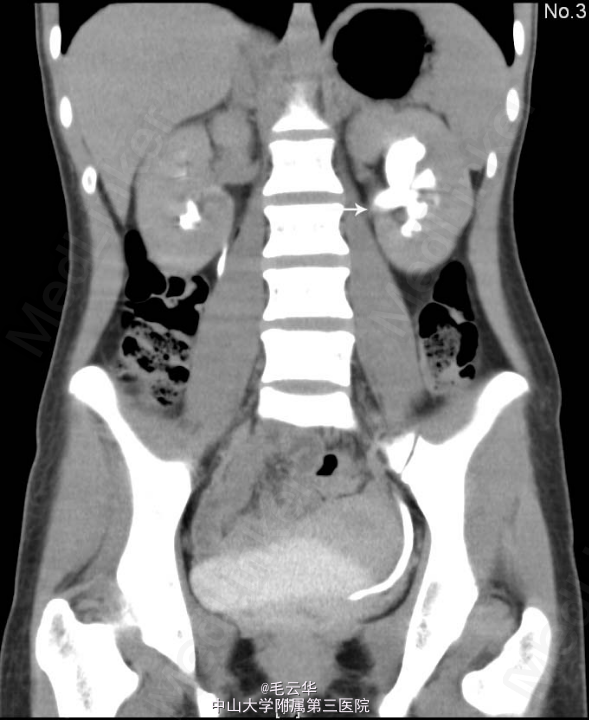

入院诊断:左肾结石 入院查尿常规RBC3003个/ul,KUB示左肾区平第2腰椎水平可见一结节状高密度影,大小为:17.8×9.9mm,考虑左肾结石。双肾CT平扫+增强+CTU示左肾下盏小结石;左侧盂管交界处结石(23×9mm),并左肾轻度积液。全麻下行左侧输尿管软镜碎石取石术,术程顺利,术后安返病房。